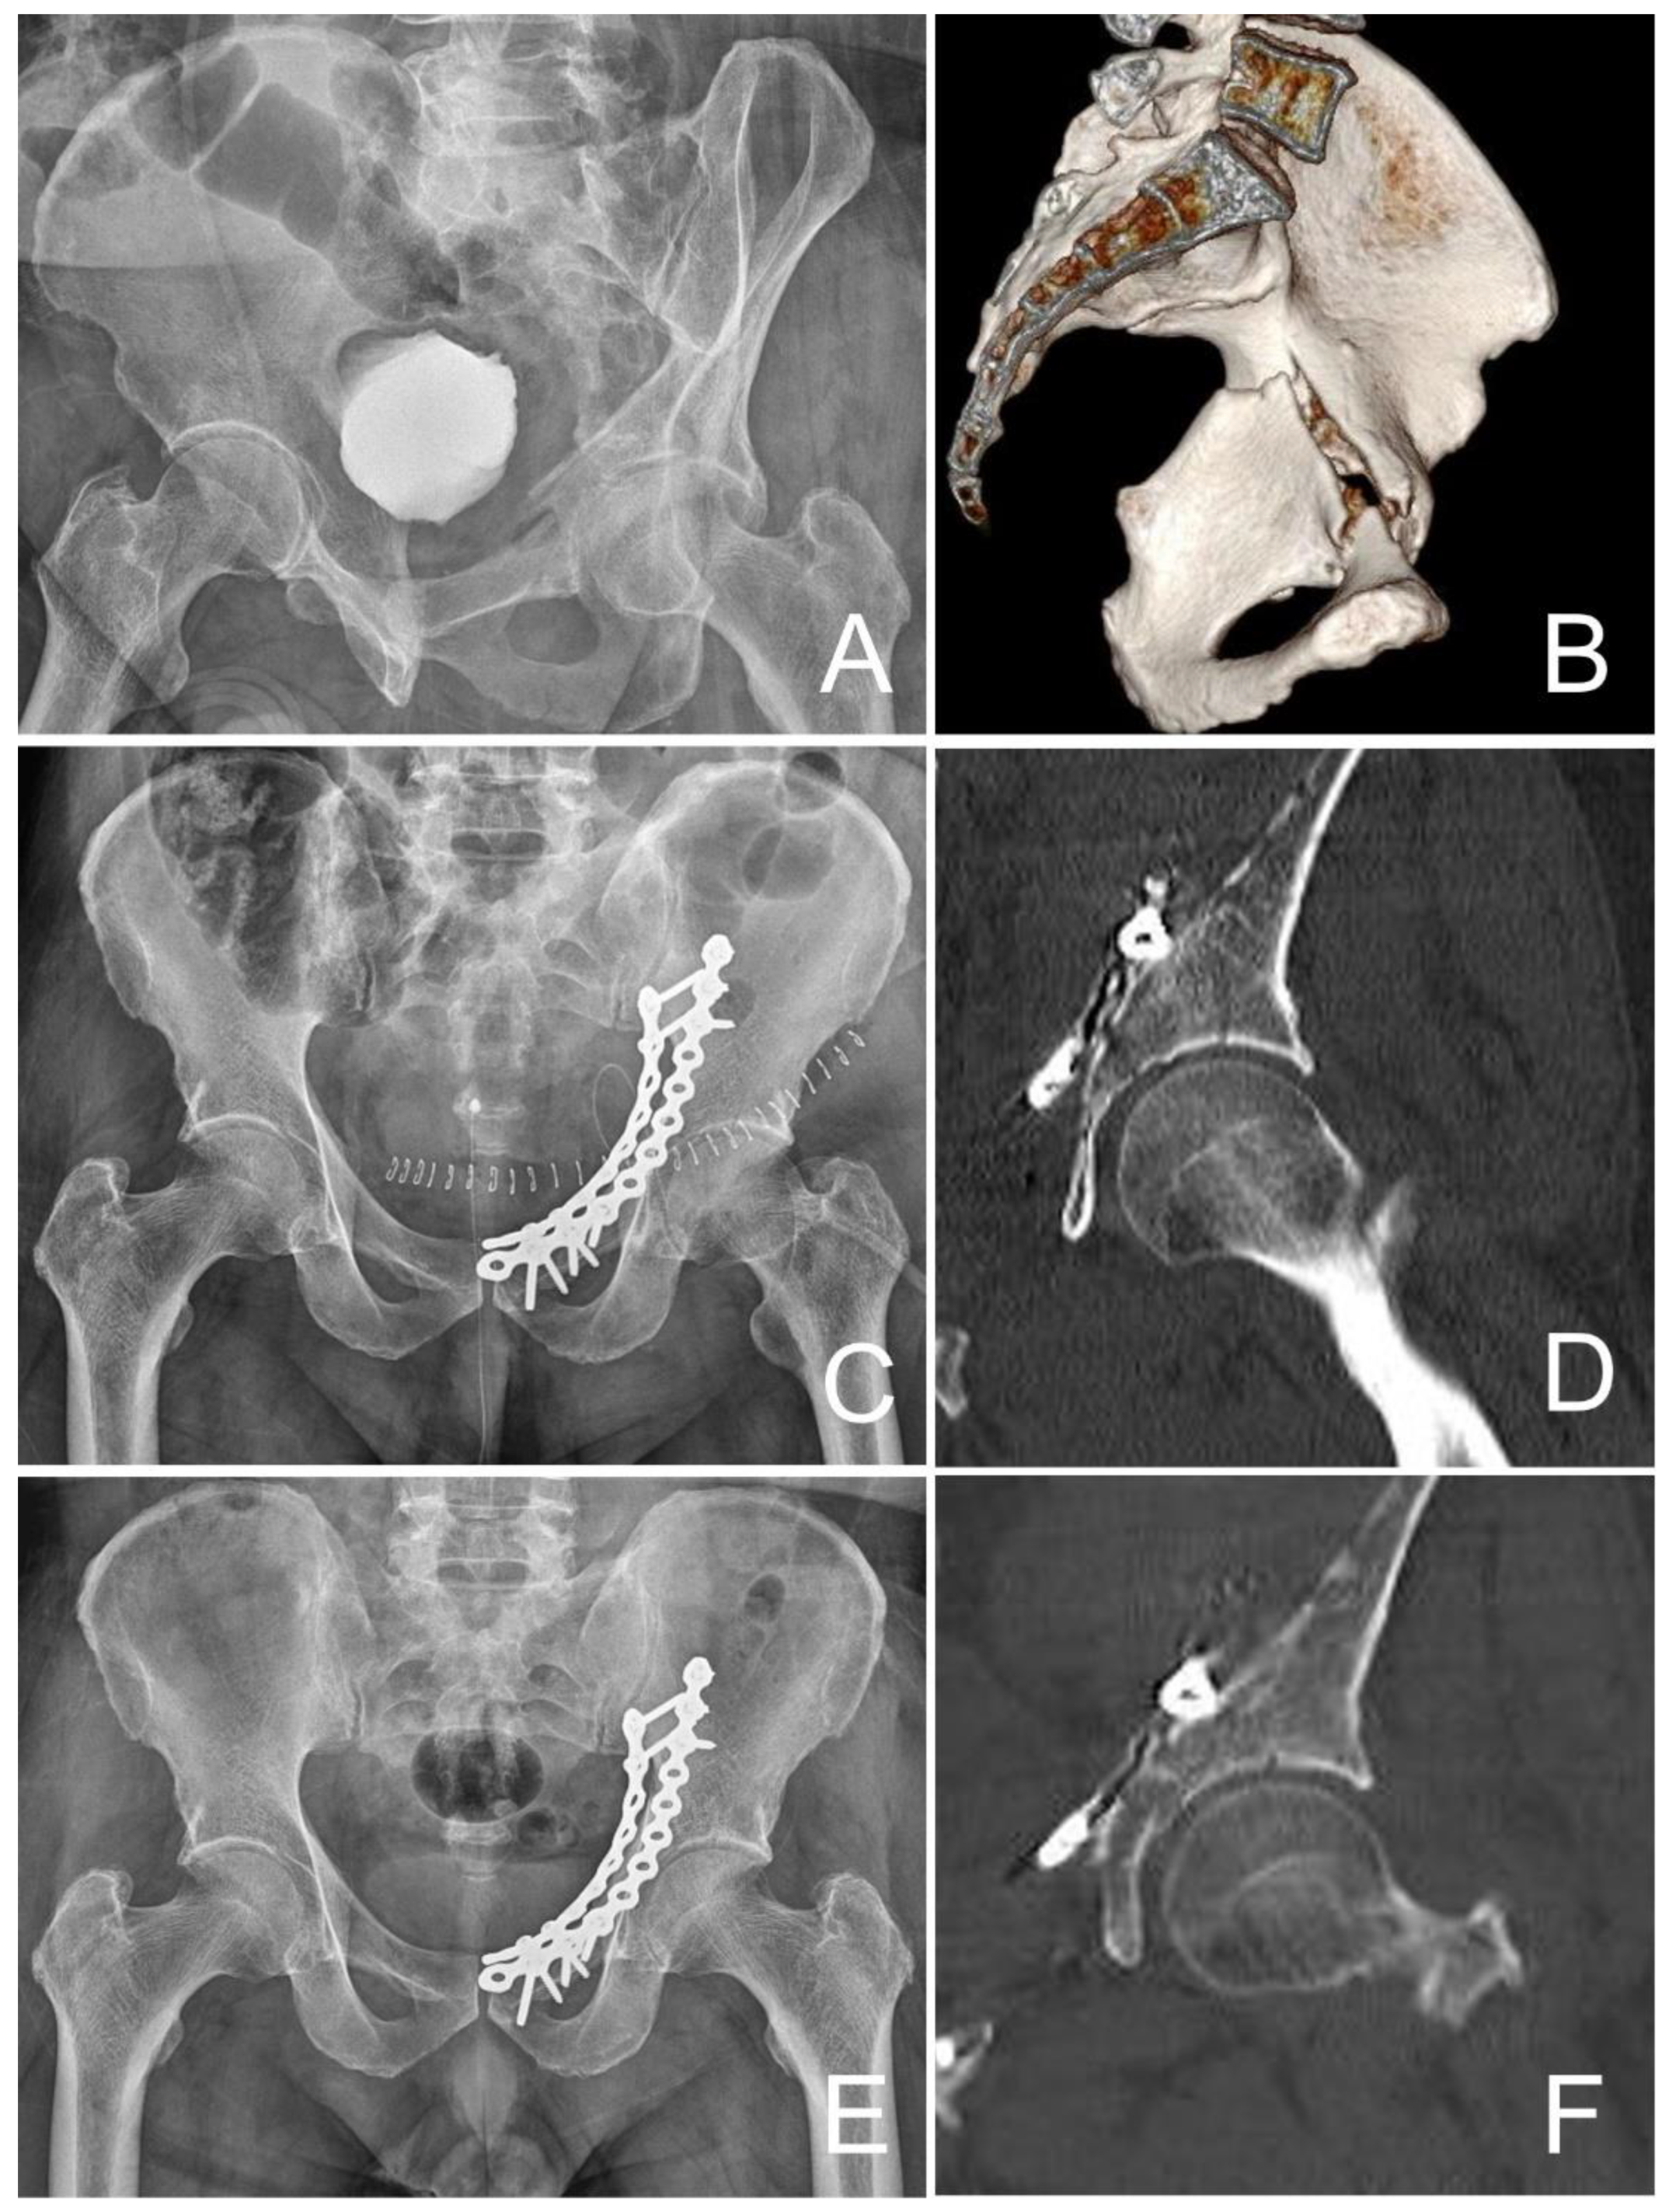

| Postoperative reduction status | |||

| Anatomical (<1 mm) | 12 | 13 | >0.05 |

| Congruent (2–3 mm) | 7 | 9 | >0.05 |

| Poor (>3 mm) | 1 | 7 | >0.05 |

| Medialization of femoral head (mm) | 0.3 | 3.9 | <0.05 * |